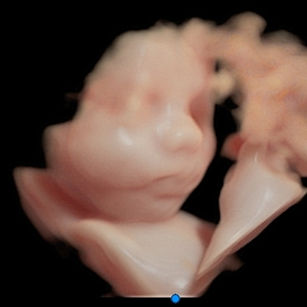

Weight: ~2.75 pounds (1.25 kg), the size of a Butternut Squash!

Length: ~15.2 inches (38.5 cm)

Movements: Strong kicks and rolls, practicing muscle control.

Vernix & Lanugo: Vernix thickening; lanugo still present.